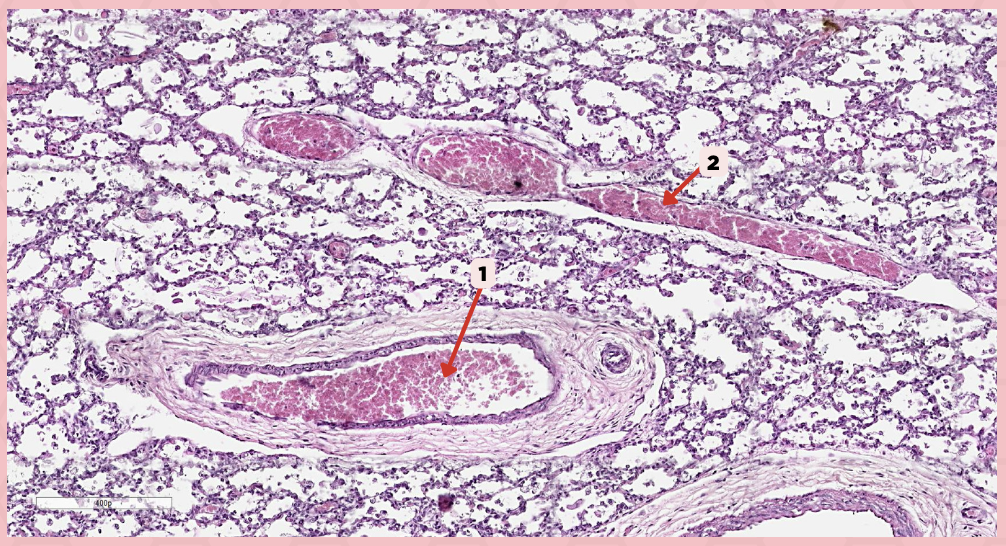

Deoxygenated blood

What type of blood does vessel No. 1 carry?

Connective tissue septae

Where would No. 2 be located?

Pulmonary artery

Identify the structure labeled as 1.

Tributary of pulmonary vein

Identify the structure labeled as 2.

Oxygenated blood

What type of blood does this vessel supply?

Bronchial artery

Identify the structure labeled as 1.